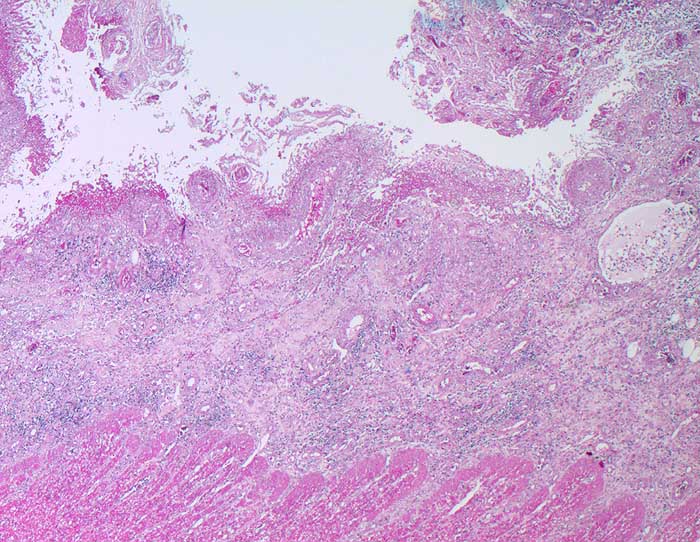

Amöbiasis

Kolon ascendens

Ulkus mit Kolliquationsnekrose und Fibrinschorf. Die Erreger sind in dieser Vergrösserung nicht zu sehen.

Die gewebsinvasiven Throphozoiten bewirken an der Schleimhautbasis eine Histolyse an der Grenze zur Muscularis mucosae unter Ablösung der Schleimhaut. Bei 90-99% der Infizierten verläuft der Infekt asymptomatisch (intestinale Darmlumeninfektion mit Erregerausscheidung). Die restlichen Patienten leiden an einer invasiven Amöbiasis. Die Krankheit kommt vor allem in den Tropen und Subtropen, seltenerweise aber auch in Mitteleuropa vor. Es gibt ein vegetatives Stadium der Trophozoiten und Zysten, die aus bis zu vier Trophozoiten gebildet werden. Im Dünndarm werden aus ingestierten Zysten Trophozoiten freigesetzt in Form von apathogenen Kommensalen, der Minutaform (12-18 Mikrometer) und der histolytischen Magnaform (bis 20-30 Mikrometer) mit Erythrophagozytose. Die Freisetzung proteolytischer Enzyme bewirkt eine Kolliquationsnekrose. Bei chronischer Ulzeration entwickelt sich ein Amöbom bestehend aus Granulationsgewebe, das den Darm einengen und ein Karzinom imitieren kann. Häufigste Komplikation ist der Leberabszess.

Histologie

25